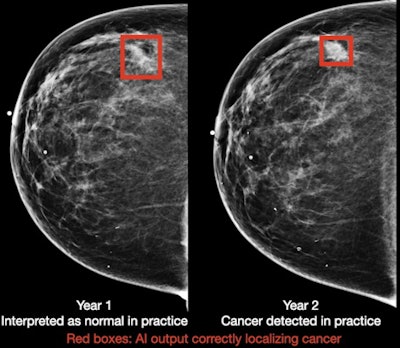

A deep-learning algorithm successfully detected breast cancer on screening mammography, in some cases as early as two years before it was diagnosed during conventional interpretation, according to research published online January 11 in Nature Medicine. The algorithm also performed well with digital breast tomosynthesis (DBT) exams.

After training the algorithm on five large datasets from the U.S., U.K., and China, the researchers compared its performance with five expert radiologists on index exams (mammograms acquired up to three months prior to biopsy-proven cancer) and "pre-index" studies (mammograms acquired 12-24 months prior to the index exam and were interpreted as negative in the clinical setting). These cases were gathered from a different population than was used to train the model.

These differences were also statistically significant (p = 0.0009 and p = 0.0008, respectively). What's more, the algorithm -- at 90% specificity -- would have flagged 45.8% of the missed cancer cases for follow-up, according to the researchers.